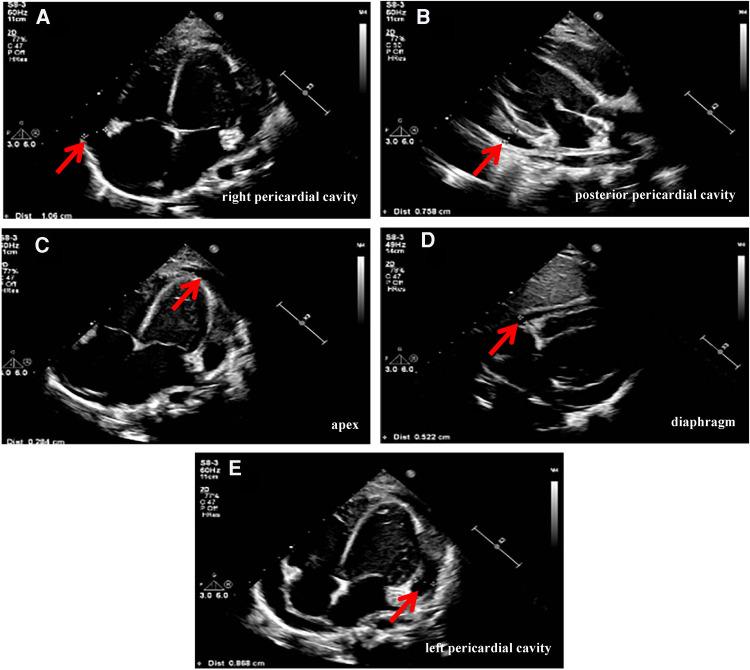

Human adenoviruses (HAdVs) can cause infection at any age but are most common in the pediatric population, especially young children and infants, with a peak incidence in infants and children from 6 months to 5 years of age. Adenovirus infection can cause severe pneumonia, but pericarditis from adenovirus infection was rare. This article reports a case of a 2-year-old patient with pericarditis caused by adenovirus infection and a moderate pericardial effusion. We detected positive adenovirus nucleic acid in the patient's blood by polymerase chain reaction assay. In addition, HAdVs were identified by metagenomics next-generation sequencing (mNGS) in blood and pericardial effusion. According to the test results and clinical practice, active symptomatic and supportive treatment was given, and finally the child recovered and was discharged from the hospital. Comprehensive and accurate diagnosis of pathogens is a prerequisite for effective treatment, and mNGS provides an effective means for diagnosing rare adenovirus myocarditis in children.

人腺病毒(HAdVs)可在任何年龄引发感染,但在儿童群体中最为常见,尤其是幼儿和婴儿,6个月至5岁的婴幼儿发病率最高。腺病毒感染可导致严重肺炎,但腺病毒感染引起的心包炎较为罕见。本文报道了1例2岁腺病毒感染所致心包炎并伴有中度心包积液的患者。我们通过聚合酶链反应检测在患者血液中检测到腺病毒核酸呈阳性。此外,通过宏基因组学下一代测序(mNGS)在血液和心包积液中鉴定出了人腺病毒。根据检测结果及临床实际情况,给予积极的对症及支持治疗,最终患儿康复出院。病原体的全面准确诊断是有效治疗的前提,而mNGS为诊断儿童罕见腺病毒心肌炎提供了一种有效手段。